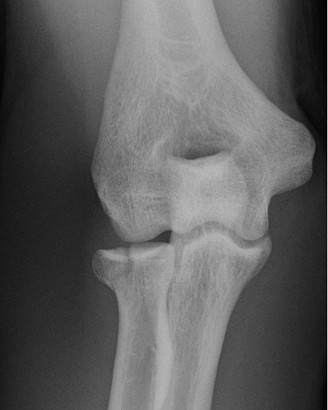

Physicians should obtain a complete set of x-rays. Special views include the modified Westpoint axillary (Fig. 2–43B) to evaluate for glenoid loss and the stryker notch view (Fig. 2–43A) to evaluate the Hill–Sachs lesion. This view brings the posterolateral defect into direct visualization. 3D CT imaging is also very useful for evaluating glenoid bone loss and estimating the size of the Hill–Sachs lesion.

--- _Figure 2–43_A: Stryker notch view. B: West point axillary view. (From Bucholz RW and Heckman JD. Rockwood and Green’s Fractures in Adults 7e. Philadelphia: Wolters Kluwer, 2009.)